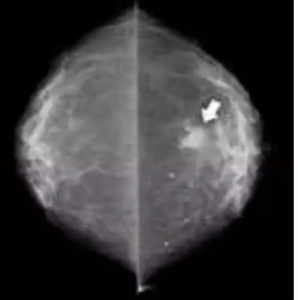

Describe ductal carcinoma in-situ (DCIS)

* —A neoplastic intraductal epithelial proliferation in the breast with an inherent, but not inevitable, risk of progression to invasive breast carcinoma.— * Common.— * Incidence has markedly increased since the introduction of breast screening programmes.

36

How often are DCIS diagnosed?

—85% are detected on mammography as areas of microcalcification.— 10% produce clinical findings such as a lump, nipple discharge, or eczematous change of the nipple (**Paget’s disease of the nipple**).— 5% are diagnosed incidentally in breast specimens removed for other reasons. —Subclassified histologically into low, intermediate and high grade.